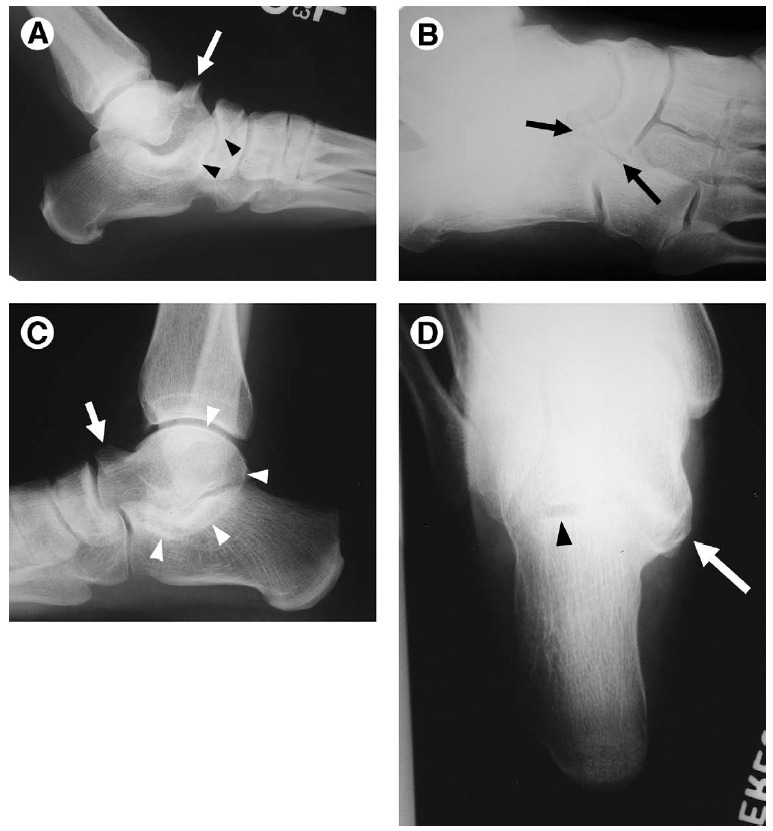

Figure 7 Calcaneal fracture.

(A) Achilles avulsion. Along with anterior process fracture depicted in Fig. 5E and extensor digitorum brevis avulsion fracture shown in Fig. 5B, Achilles tendon avulsion (arrow) is classified as an “extraarticular” calcaneal fracture. This fracture is more common in diabetic patients and patients with renal osteodystrophy.

(B) Joint depression-type fracture. Resulting from axial load injury, the “joint depression type” is the most common of the “intraarticular” calcaneal fractures. The talus is driven into the calcaneus, displacing the subtalar articular surface into the calcaneal body, flattening Boehler’s angle (lines), and typically creating an anteromedial sustentaculum fragment

and a posterior tubercle fragment, with varying degrees of comminution and medial-to-lateral widening. The “tonguetype

fracture” is described when a curvilinear fragment extending to the posterosuperior calcaneus is rotated downward.

Figure 8 Stress fracture.

(A) Calcaneal fatigue fracture. Fatigue fractures are overuse injuries occurring in normal bone. The most common

locations in the ankle and foot are the calcaneus (arrows) and the distal second metatarsal shaft. The fracture line is sclerotic, reflecting microcallus forming along the lines of stress perpendicular to the main trabecular orientation.

(B) Tibial insufficiency fracture. Insufficiency fractures occur in abnormal (ie, osteoporotic) bone undergoing normal stresses. AP oblique (mortise view) view of the ankle shows demineralized bones with a horizontally oriented dense line (arrowheads) across the distal tibial epimetaphysis, representing an insufficiency fracture.